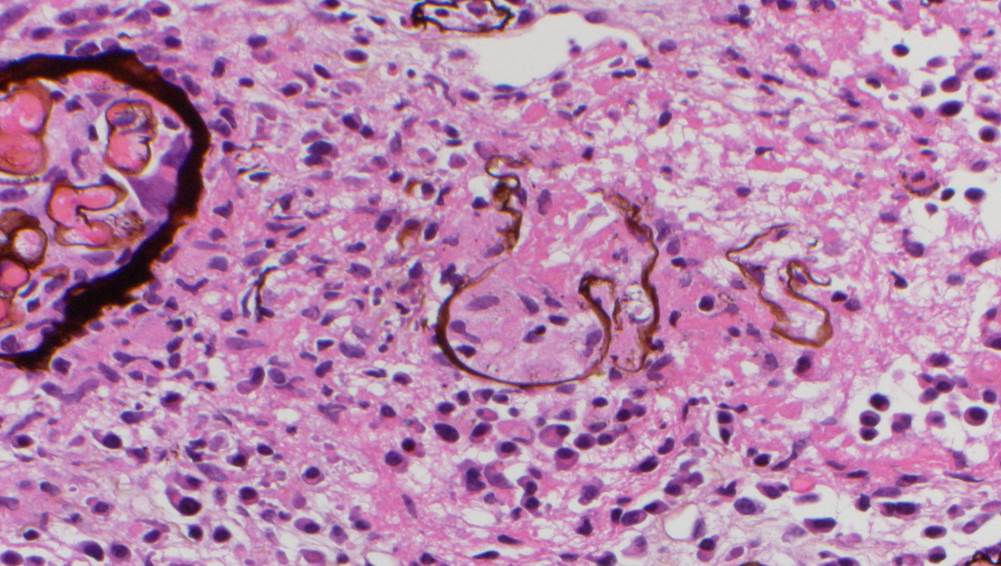

A renal allograft biopsy is essential to differentiate adenoviral nephritis from that of acute rejection or other pathology. Typical light microscopic findings in adenovirus nephropathy include tubular cell necrosis (with tubular basement membrane rupture) associated with severe interstitial inflammation (sometimes with granuloma formation), focal interstitial hemorrhage and viral cytopathic changes including peripheral condensed chromatin, basophilic nuclear inclusions and nuclear enlargement. In some cases such as ours, viral inclusions are not identified, presumably because of the focal nature of viral infection in the kidney. Immunoperoxidase staining can be used to confirm the presence of adenovirus within the nuclei, and to a lesser degree, within the cytoplasm of tubular epithelial cells; although weak, our case showed positive staining. These viral particles are visible under electron microscopy, measuring approximately 75 nm, however they were absent in our patient. Diagnosis in such cases can be clinched by urine examination showing white cell casts and decoy cells, and PCR on the urine testing positive for viral DNA.